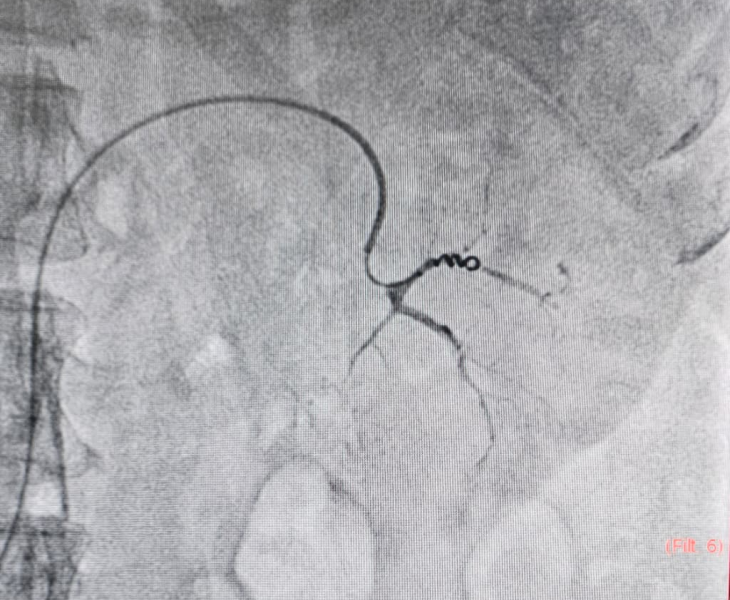

- Catheter angiography: contrast is injected to locate the pseudoaneurysm and bleeding source.

- Super‑selective catheterisation: a microcatheter is advanced into the specific branch feeding the pseudoaneurysm.

- Embolization: coils and/or other embolic agents are deployed to stop blood flow to the pseudoaneurysm.

- Post‑embolization check: repeat angiography confirms complete sealing with preserved flow to normal tissues.